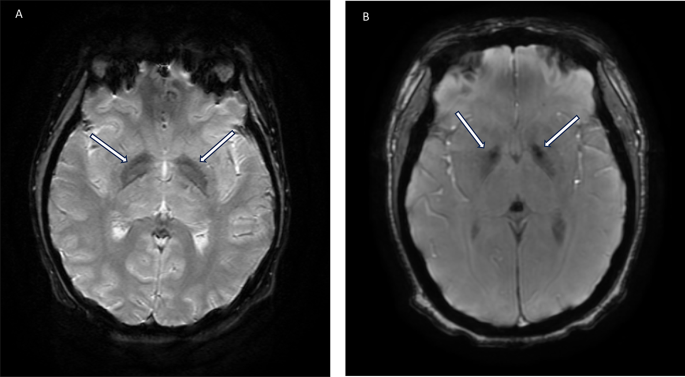

Neurodiagnostic data is also reported in Table 2. The rate of EEG abnormalities was 30% (n = 40), with the large majority being diffuse bilateral slowing (33/40, 83%). Neuroimaging abnormalities were detected in 33% (n = 54) of individuals, with the majority having bilateral susceptibility-weighted imaging (SWI) signal abnormalities in the basal ganglia (40/54, 74%). Representative imaging findings are presented in Fig. 1. Compared to a cohort of individuals with DSwR who had neuroimaging performed for any reason outside of the neonatal period, there was a statistically significant higher incidence of T2 signal prolongation and gradient echo sequences (GRE)/SWI signal abnormalities (p < 0.001, 95%CI: 1.70–5.87). The rate of abnormalities on lumbar puncture was 21% (n = 34). The most frequent abnormalities in the cerebrospinal fluid were elevated CSF protein and elevated IgG index which were present in seven individuals each (14%). Independently, there were seven individuals with both elevations in CSF total protein and IgG index (7%). Individuals with DSRD who had CSF abnormalities demonstrated greater disease severity at diagnosis with a median BFCRS of 29 and NPI-Q total score of 45 compared to those without which were 21 and 30, respectively (p = 0.02, 95%CI: 1.07–2.64; p < 0.001, 95%CI: 1.39–6.21). This difference was not observed in individuals with EEG (p = 0.41 and p = 0.66) or MRI (p = 0.37 and p = 0.22) abnormalities.

SWI signal abnormality in the basal ganglia of individuals with DSRD. Legend: white arrows correspond to SWI signal abnormalities in the bilateral basal ganglia.